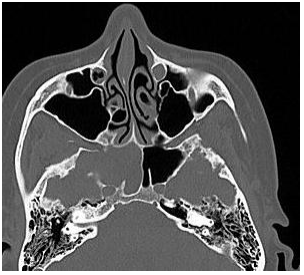

Mulher, 42 anos de idade, IMC de 35 kg/m2. Refere rinorreia

hialina à esquerda, que se iniciou abruptamente, há um ano.

Disse que “pinga secreção do nariz”, parecendo água,

quando abaixa. Nega outros sintomas nasossinusais, e nega

trauma prévio. Endoscopia não evidencia lesões em cavidade

nasal. Apresenta a tomografia de seios da face, com o achado

a seguir:

Diante do quadro, qual o exame laboratorial que confirma o diagnóstico?